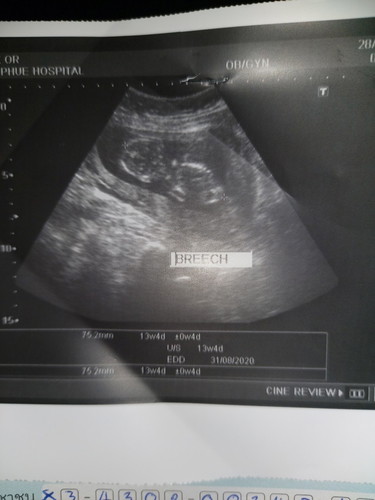

13w4dลูกนอนคว่ำแบบนี้ปกติไม้คะหมอไม่บอกอะไรเลยนัดเดือนหน้าไปฟังผลอีกทีค่ะ